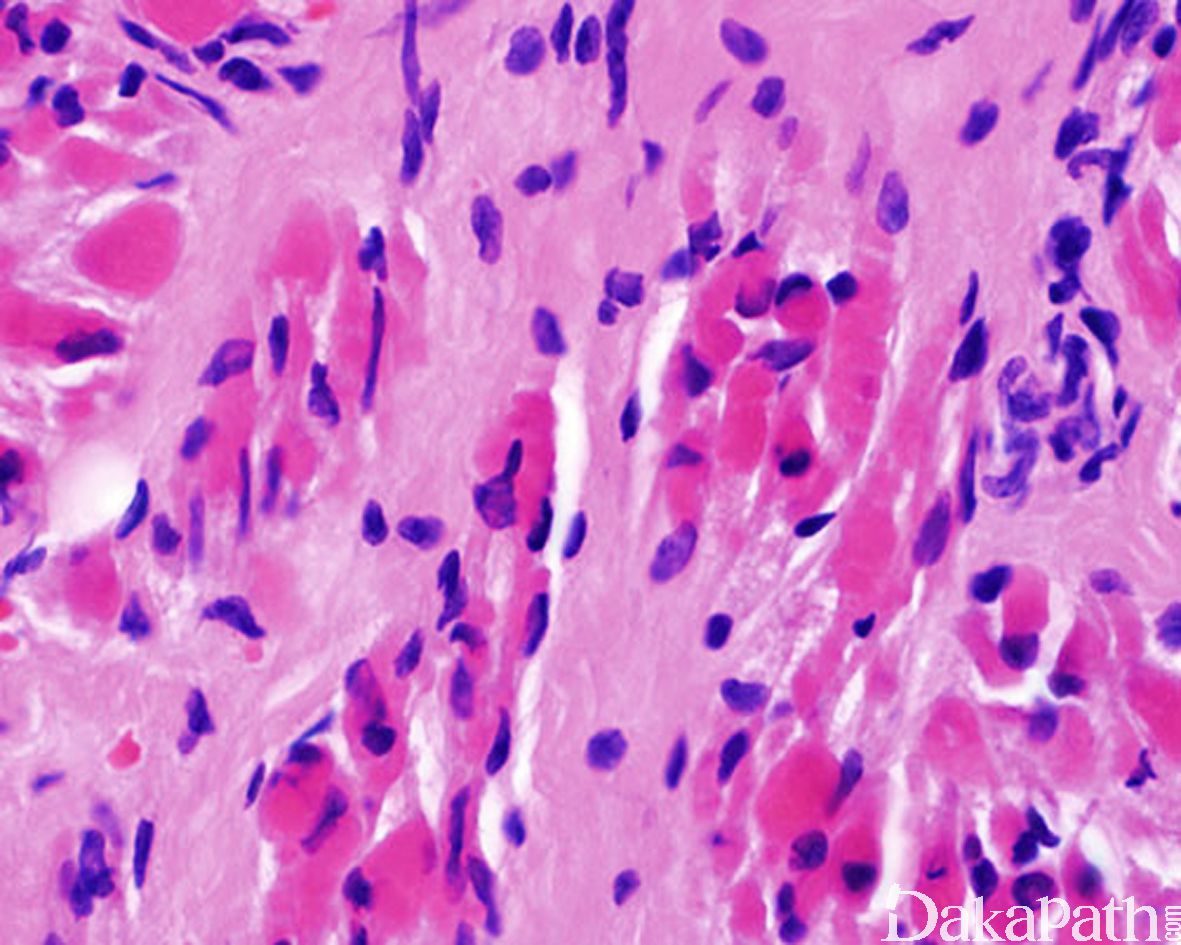

- 早期胖纤维母细胞、肌纤维母细胞弥漫性增生,排列紊乱,分离横纹肌组织,使之扭曲、变形,间质呈黏液样或胶原化,可见混杂退变的肌巨细胞;

- 晚期细胞数量明显减少,而间质内的胶原纤维大量增加,类似疤痕组织。